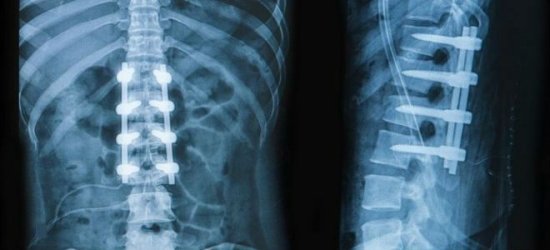

Компьютерная томография является эффективным и высокоинформативным способом выявления различных структурных изменений в позвоночнике, вызванных травматизацией, инфекционным процессом, опухолевыми образованиями, остеопорозом и другими заболеваниями. В основе миелографии лежит применение контрастирующего вещества. Метод применяют при подозрении на стеноз позвоночного канала, грыжевых образованиях, опухолях и других патологических процессах в позвоночнике.

После обращения к травматологу потребуются лабораторные и аппаратные исследования, включающие в себя: анализ мочи и крови, рентгенографию, МРТ, электрокардиограмму . При лечении применяются как классические методы (фиксация и восстановление повреждённого позвонка), так и хирургические.